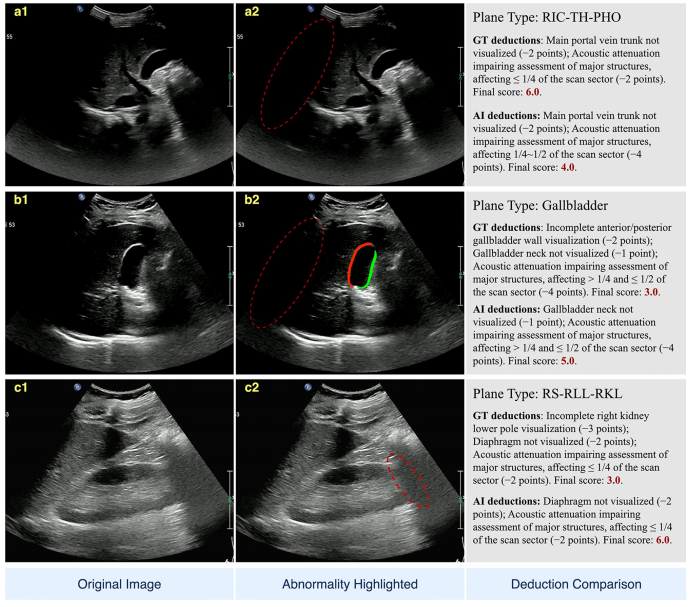

对临床最关注的"优秀"级(8-10分)图像,Qwen2-vl-2B达到85.11%的判读准确率。混淆矩阵显示,各主干模型在优秀/良好(6-8分)区间的分类一致性达92%,但在中等/较差(4-6分)区间存在约15%的误判,主要源于声衰减区域的扣分边界模糊(如图6所示)。